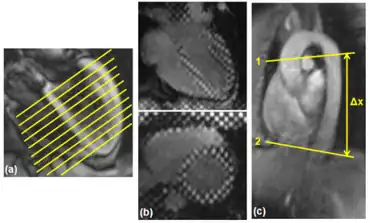

| In those with HFpEF, the left ventricle of the heart (large chamber on right side of the picture) is stiffened and has impaired relaxation after pumping blood out of the heart. | |